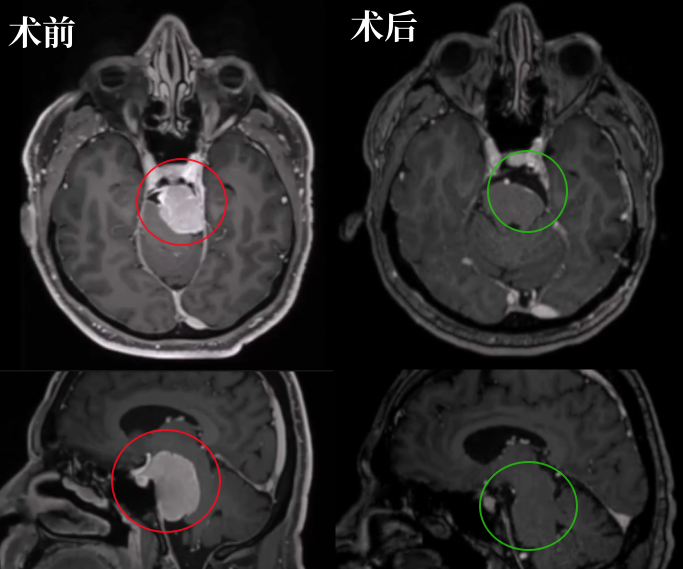

第一步是术前精准评估:通过MRI确认脑干无水肿,CT扫描逐一评估肿瘤钙化程度、岩尖气化范围、颈静脉球与内耳道的位置关系,每一个解剖细节,都是术中安全操作的前提。

术后MRI显示:肿瘤几乎完全切除,脑干压迫已彻底解除。术后CT未见任何并发症,颅骨修复状态良好。

术后恢复过程中,Bruno出现了一过性不完全性滑车神经麻痹,低头时有轻微复视,但该症状在术后3个月内完全消失;因中耳炎引起的轻度听力下降,也在术后6个月时完全恢复正常。